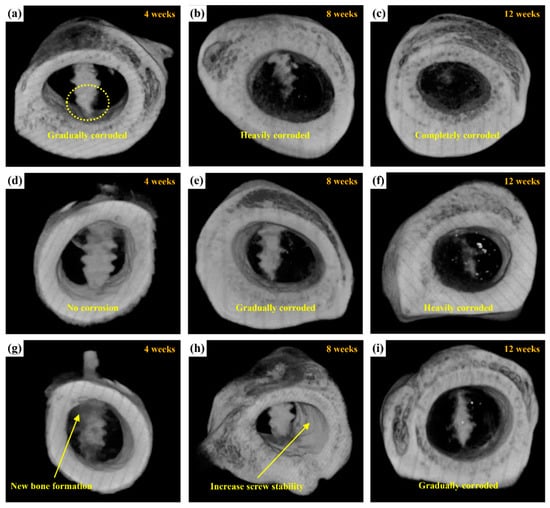

2.3.2. Radiological Examination

2.3.3. Micro-CT Scanning